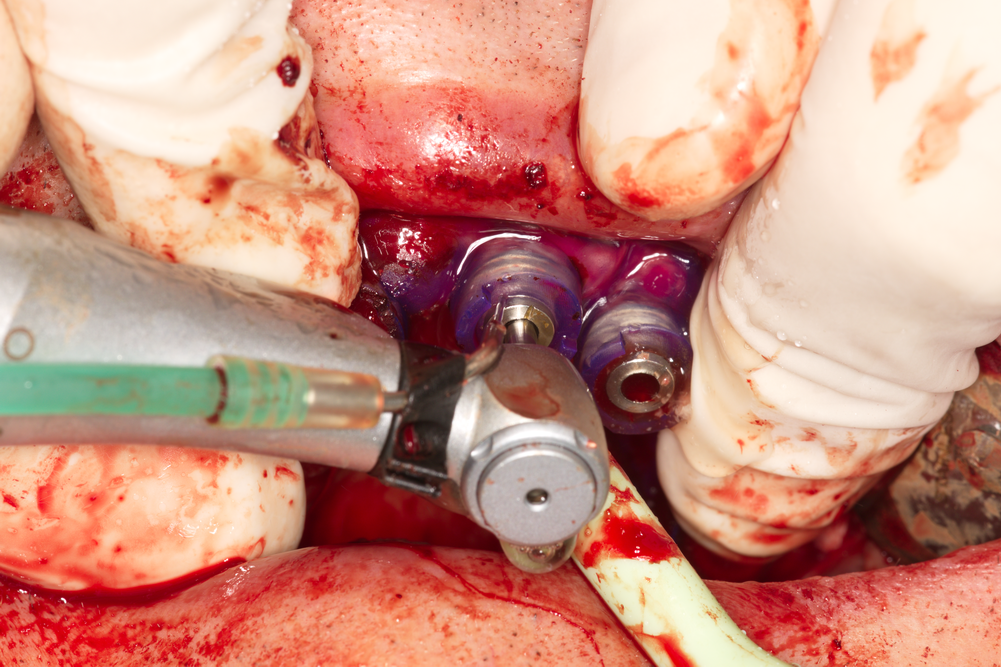

Развиване на покривния винт на двучастов дентален имплант. Тази процедура се извършва след пълната остеоинтеграция на денталния имплант - т.е. след приключването на оздравителния процес. Тогава се поставя имплантатната надстройка (абатмънт или супраструктура) и се изработва съответното възстановяване - коронка (както е в горния случай), мостоносител или снемаема протеза. Именно в това е смисълът на поставянето на един зъбен имплант - не да се имплантира изкуствено тяло в костта и то да остане там, а да се осигури трайна и надеждна задръжка на различните протезни конструкции. Имплантатната платформа се явява единствено посредник между човешкия организъм и изкуствения зъб. Пациентът няма да дъвче и да се усмихва с вътрекостния винт - той има нужда в най-елементарния случай поне от единична корона.

Снимка на поставянето на интраосален (вътрекостен) зъбен имплант. В огромен процент от случаите (над 99 % в световен мащаб) в съвременната имплантология се използват именно вътрекостните импланти - интраосален всъщност означава вътрекостен. В миналото е имало опити за поставяне и на други видове импланти - трансосални и субпериостални, но с течение на времето като истински надеждно и трайно лечебно средство се е доказал класическият вътрекостен имплант - независимо дали е двучастов или едночастов. Към момента няма информация за приложението на трансосални импланти някъде по света; субпериостални импланти обаче се прилагат в ограничени случаи на силно изразена атрофия - предимно на долна челюст. Освен това съществуват и субмукозни и трансосални импланти; те обаче се поставят изключително рядко. Първият тип импланти се поставя само под лигавицата и поради това механичната им задръжка не е надеждна; вторият тип пробожда костта в пълна дебелина, което прави имплантацията изключително травматична, а оздравителният процес - бавен и не особено приятен. Поради това трансосалните импланти намират приложение предимно в областта на ортопедията и травматологията - като средство за фиксация на фрактурирани кости, за костни дистракции, за корекция на различни вродени малформации и много други.

Поставени интраосални импланти от системата TBR - Франция. Нашият екип е привърженик на поставянето на по възможност по-голям брой импланти - навсякъде, където това е възможно. Предимствата на подобен лечебен подход са безспорни - намалява се механичното претоварване, елиминират се мостовите тела (под които се задържа зъбна плака), намалява се честотата на протетичните усложнения и като цяло постигнатият резултат е по-траен и по-стабилен с течение на времето. Вижда се циркониевият пръстен в областта на имплантатната шийка. Той служи за адаптация на меките тъкани и при добро планиране и изпълнение на клиничния случай е възможно да се получат наистина впечатляващи естетични резултати. Проблем представлява голямата височина на имплантатната шийка - понякога около нея се формира постоперативен хематом и това удължава заздравителния процес. Това обаче се случва единствено при опит за покриване на циркониевия пръстен и надлежащия винт с лигавица и периост - тогава субмукозно остава значително по обем празно пространство, което се изпълва с кръв. Имплантите на системата TBR са от типа tissue level, а не bone level - т.е. имплантатната шийка при тях трябва да се разположи на нивото на меките тъкани, а не под нивото на костта. Всичко това изисква запознаване на хирургичния протокол в детайли и стриктно спазване на всички предписания и концепции на производителя - тъй като те са отдавна изпитани във времето и освен това са обект на непрекъснати клинични проучвания и усъвършенстване. Нашият екип винаги се опитва да прави съответните аналогии с цел по-добра визуализация на описаната материя. В този случай се прилага една сентенция от областта на авиацията - всичко, което знаем от практическа гледна точка, е писано с много кръв; в областта на хирургията и медицината като цяло това твърдение е валидно с особено голяма сила.